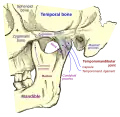

Articulação da mandíbula. Aspecto lateral.

Articulação da mandíbula. Aspecto lateral. -